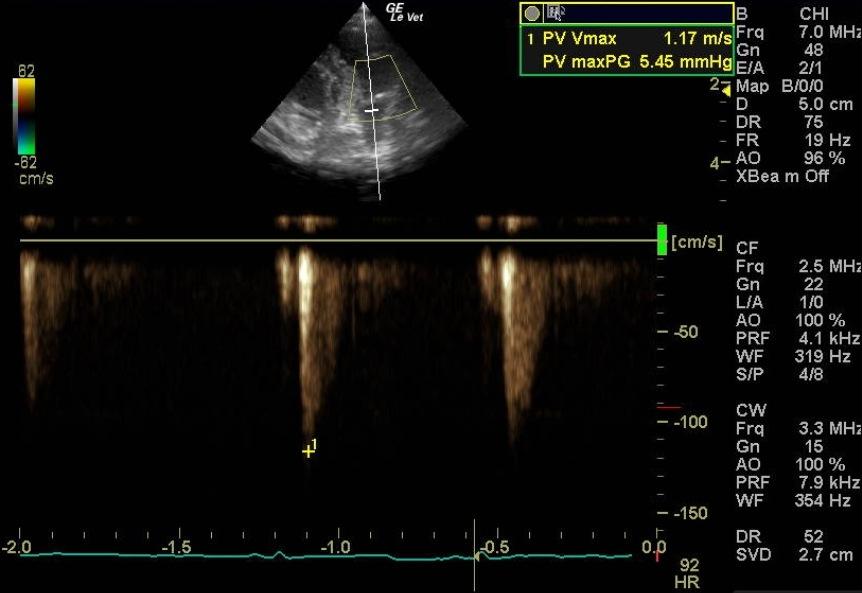

A 1-year-old female spayed toy poodle dog presented for evaluation of bradycardia. Blood pressure was within normal limits. Survey thorax radiographs showed normal size and shape of the cardiac silhouette and left atrium. The vertebral heart sum was 10.2, and a mild interstitial lung pattern was noted.